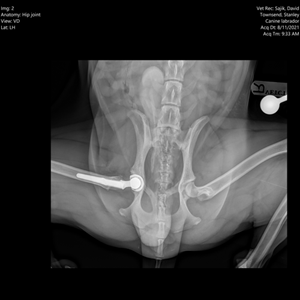

Total hip replacement in Stanley the Labrador

Our specialist orthopaedic surgeon, David Sajik, performed Stanley’s total hip replacement surgery, which consisted of the placement of a prosthetic acetabular component (socket) and femoral prosthesis (ball) replacing Stanley’s natural ‘ball and socket’ hip joint.

Images show ventrodorsal extended-leg and frog-leg views of hip joints.